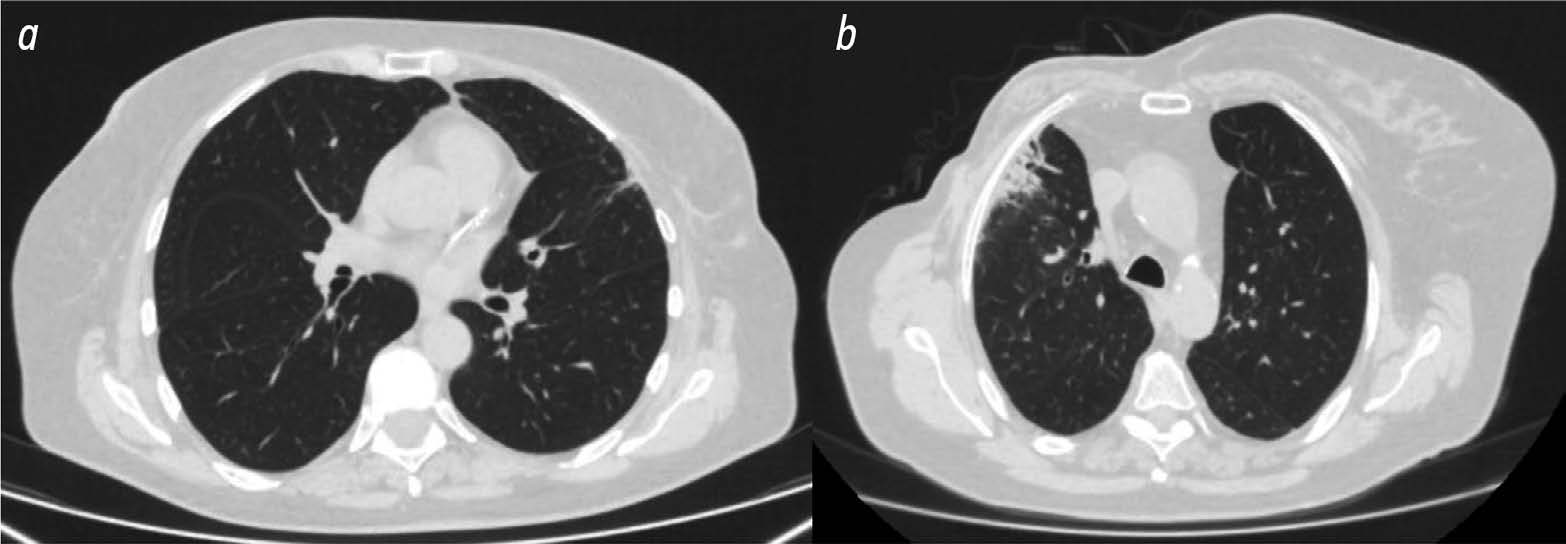

Use of radiomics and dosiomics to identify predictors of radiation induced lung injury

BACKGROUND: Radiomics is a machine learning based technology that extracts, analyzes, and interprets quantitative features from digital medical images. In recent years, dosiomics has become an increasingly common term in the literature to describe a new radiomics method. Dosiomics is a texture analysis method for evaluating radiotherapy dose distribution patterns. Most of the published research in dosiomics evaluates its use in predicting radiation induced lung injury.

AIM: The aim of the study was to identify predictors (biomarkers) of radiation induced lung injury using texture analysis of computed tomography (CT) images of lungs and chest soft tissues using radiomics and dosiomics.

MATERIALS AND METHODS: The study used data from 36 women with breast cancer who received postoperative conformal radiation therapy. Retrospectively, the patients were divided into two groups according to the severity of post radiation lung lesions. 3D Slicer was used to evaluate CT results of all patients obtained during radiation treatment planning and radiation dose distribution patterns. The software was able to unload radiomic and dosiomic features from regions of interest. The regions of interest included chest soft tissue and lung areas on the irradiated side where the dose burden exceeded 3 and 10 Gy.

RESULTS: The first group included 13 patients with minimal radiation induced lung lesions, and the second group included 23 patients with post radiation pneumofibrosis. In the lung area on the side irradiated with more than 3 Gy, statistically significant differences between the patient groups were obtained for three radiomic features and one dosiomic feature. In the lung area on the side irradiated with more than 10 Gy, statistically significant differences were obtained for 12 radiomic features and 1 dosiomic feature. In the area of chest soft tissues on the irradiated side, significant differences were obtained for 18 radiomic features and 4 dosiomic features.

CONCLUSIONS: As a result, a number of radiomic and dosiomic features were identified which were statistically different in patients with minimal lesions and pulmonary pneumofibrosis following radiation therapy for breast cancer. Based on texture analysis, predictors (biomarkers) were identified to predict post radiation lung injury and identify higher risk patients.